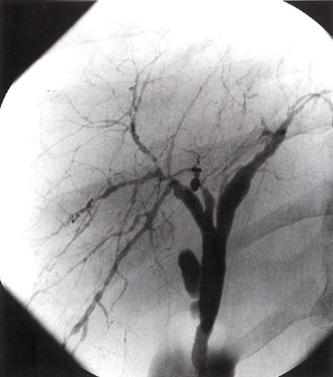

Coronariografía (angiografía coronaria)

Es una prueba invasiva y definitiva para valorar la gravedad de la enfermedad coronaria (gold estándar).

Se indica en casos de angina severa (grado III – IV), falta de respuesta al manejo médico, alto riesgo en pruebas funcionales o previo a la revascularización.

Si el paciente es refractario al manejo médico o presenta datos de alto riesgo en las pruebas funcionales, el siguiente paso sería la coronariografía con miras a la revascularización coronaria, donde se disponen de dos técnicas: